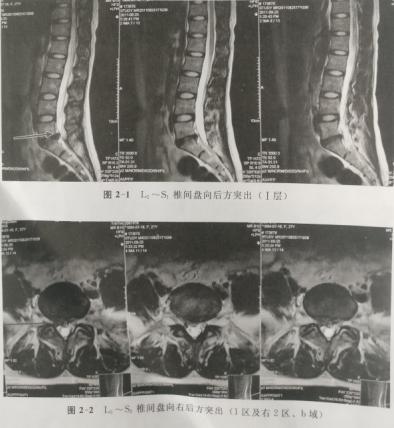

病例1.李某,男,37岁,于2011年5月7日确诊为腰椎间盘突出症,磁共振显示L5--S1椎间盘向左后方脱出并游离于L5椎体后方。患者因工作不允许离开岗位且无明显神经损害体征,行保守治疗并随访,症状逐渐减轻。2012年4月20日复查磁共振突出髓核明显缩小,几乎消失。

下面将某疼痛学杂志的报道及图片展示如下;